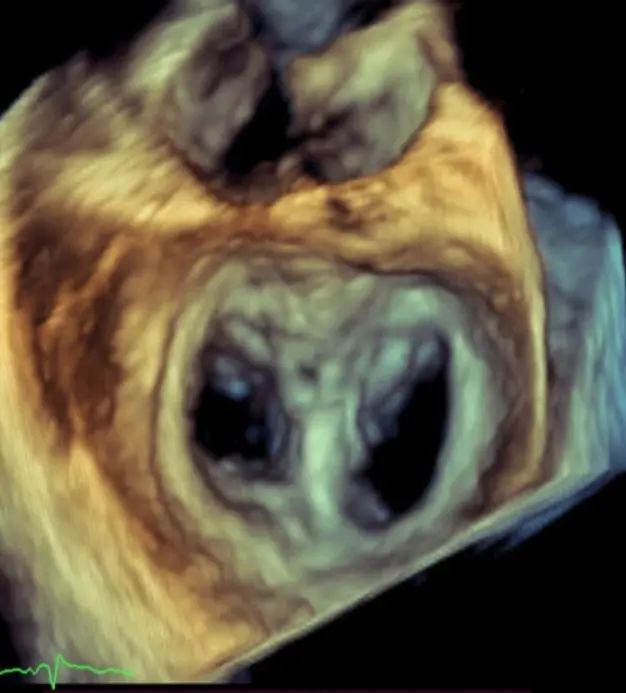

图1:患者术前TEE Biplane提示重度二尖瓣功能性反流

患者为63岁男性,罹患多支冠心病,既往发生急性心肌梗死,并曾接受两次PCI手术,存在缺血性心脏病继发的重度二尖瓣功能性反流。患者虽接受了最佳药物治疗且药物剂量已经调整到最大耐受剂量,但仍有明显症状,反复因心衰发作住院治疗,纽约心功能III级,且合并高血压、肾功能不全、室性早搏等合并症。超声(TTE/TEE)提示重度功能性二尖瓣反流(4+),缩流颈宽约7x15mm,有效反流口面积约0.67cm2;全心扩大(左室舒张末前后径62mm),左室壁运动幅度明显减低,LVEF 31%,二尖瓣前后叶活动尚可,瓣叶未见明显挛缩及活动受限,合并三尖瓣反流及肺动脉高压。患者STS评分8.92分,外科手术风险高危。心脏团队经过对患者病情和二尖瓣解剖的全面评估与讨论,决定采用JensClip瓣膜夹系统为患者进行二尖瓣缘对缘修复手术,以改善患者的二尖瓣反流及临床症状。